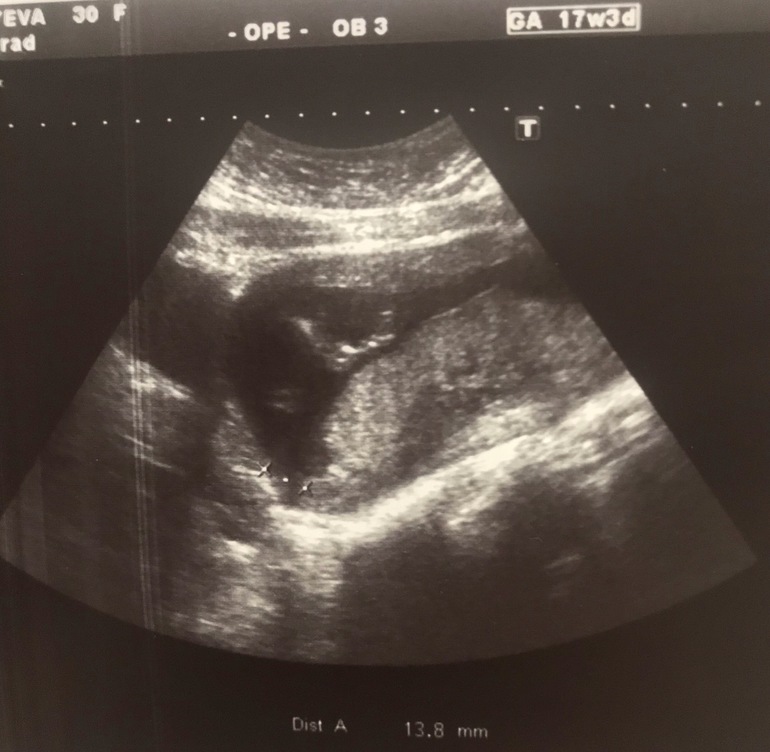

Девченки кто разбирается гляньте фото УЗИ))

УЗИ, КТГ, доплерА то нам выдали нам с мужем без врача не спросили даже))) вертели смотрели но так и не поняли что это))) срок на момент узи 17,3)

Вооот и я смотрю и думаю если это полосочка что измеряли между ножками то больше на девочку похожа, а узистка сказала что будет мальчик)))

Это бедро которое большое ))) и вторую ножку не видно )) и как бы они раздвинуты

Нашла фото УЗИ на 17 неделях.

По фото это попа и живот ребенка, может пол смотрели?

Тоже ничего не пойму, но там явно что-то измеряли, и это что-то 13,8 мм.